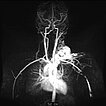

Dynamische, kontrastmittelunterstützte, zeitlich hochaufgelöste MR-Angiographie; Darstellung 46 s nach intravenöser Kontrastmittelapplikation. Das Kontrastmittel hier noch vorwiegend im kleinen Kreislauf der Lunge (Frühphase).

Dynamische, kontrastmittelunterstützte, zeitlich hochaufgelöste MR-Angiographie; Darstellung 52 s nach intravenöser Kontrastmittelapplikation. Bereits 5 s später fließt das Kontrastmittel sofort durch die arteriovenöse Malformation hindurch, eine Drainagevene ist ebenfalls bereits direkt kontrastiert. Typischer, extrem schneller Durchfluss einer arteriovenösen Malformation als Fast-flow-Läsion.

Dynamische, kontrastmittelunterstützte, zeitlich hochaufgelöste MR-Angiographie; Darstellung 57 s nach intravenöser Kontrastmittelapplikation. Weitere 5 s später nochmals bessere Darstellung des venösen Abstroms aus der arteriovenösen Malformation.